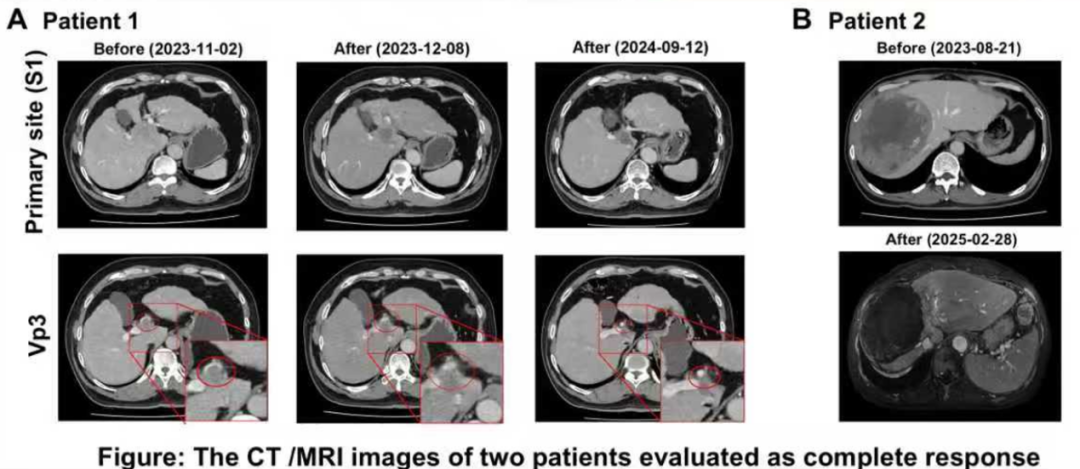

两例被评估为完全缓解患者的CT/MRI图像

疗效评估:客观缓解率(ORR)达到85.7%(6/7),其中治疗区域的ORR更是高达100%。具体而言,完全缓解(CR)率为28.6%(2/7),这两例患者的CR状态持续了9个月;部分缓解(PR)率为57.1%(4/7)。仅1例患者(14.3%)出现疾病进展(PD)。

安全性评估:没有患者出现3级及以上不良事件(AE)。最常见的不良事件是腹痛和呕吐,且所有并发症均可控。

90Y-SIRT联合Atezo-Bev治疗uHCC,展现出令人鼓舞的局部ORR(100%)和良好的安全性。这些初步发现有待未来在更大样本量的队列中进一步验证,以明确该联合方案的最佳治疗顺序及治疗时长,为临床实践提供更可靠的循证依据。